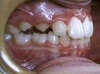

Ce décalage entraîne l'impossibilité de couper les aliments avec les dents de devant qui ne se touchent pas et qui sont inesthétiques et le risque de fracture des incisives du haut. L'orthodontie s'impose dès 7 ans et demi à 8 ans avec la présence des incisives et premières molaires définitives.

Ce premier temps d'orthodontie interceptive est terminé avant même l'arrivée de toutes les dents définitives et la chute de toutes les dents de lait. Il permet de réduire le risque de fracture des incisives supérieures, d'assurer l'incision des aliments et d'améliorer le sourire et le profil du visage.